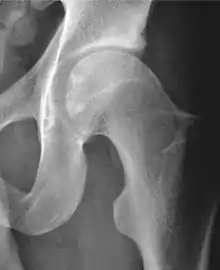

Projectional radiography ("X-ray")is often considered first line for FAI.[10] Anterior-posterior pelvis and a lateral image of the hip in question should be attained.[10] A 45-degree Dunn view is also recommended.[10][19]

| Measurement | Image | Target | Normal value |

|---|---|---|---|

| Center-edge angle of Wiberg | ![]() |

The superior-lateral coverage of the femoral head. | |